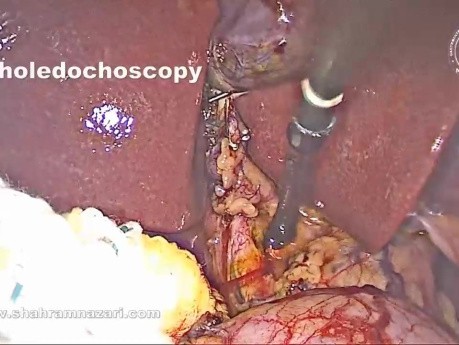

Pose d'un Stent Antérograde du Cholédoque...

L'exploration laparoscopique de la voie biliaire principale (ELVBP) s'est avérée être un traitement sûr, efficace et rentable de la lithiase biliaire. Après ELVBP, la clairance peut être évaluée par cholangiographie...